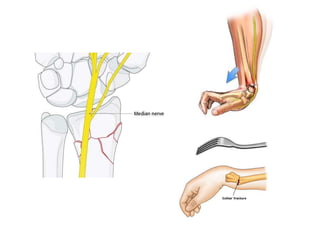

• Watch median nerve symptoms

• Acute carpal tunnel syndrome

• Median nerve neuropathy(CTS)

After reduction • Immobilizedby slab (short arm /long arm) with wrist in neutral position • Check X ray confirm to acceptable reduction • Watch median nerve symptoms • Follow up x ray needed in 1-2 wk to evaluated reduction • Change to short arm cast after 2-3 wk ,continue until fracture healing

After reduction • Outcome •Repeat closed reductions have 50% less than satisfactory results • Complication • Acute carpal tunnel syndrome • EPL rupture